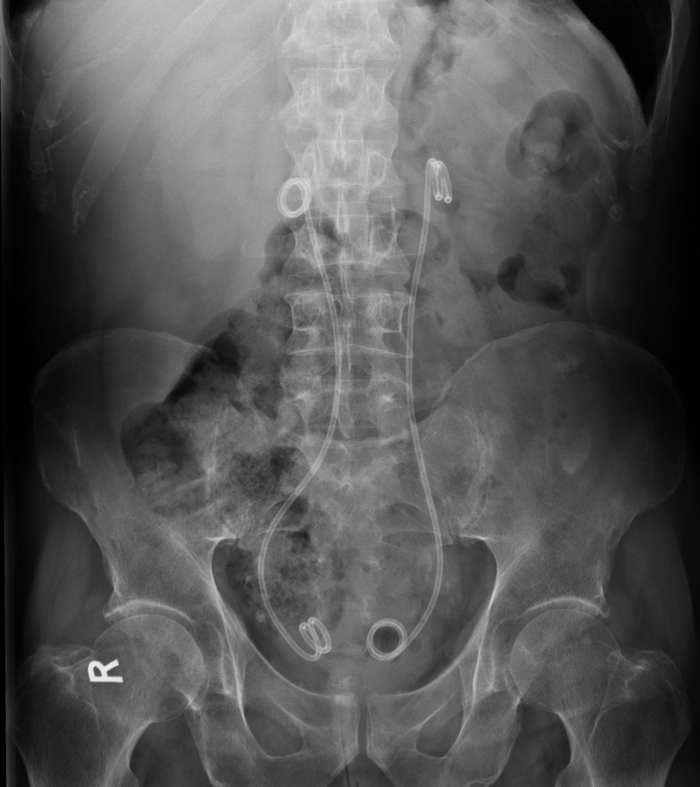

Plain radiographs are of limited use in the diagnosis. If stents are in place, or excretory phase imaging is performed, medial deviation of the ureters may be seen (Figure 1). Medial deviation of the ureters occurs due to the fibrotic tissue pulling the ureters medially, usually in the middle third at the level of L3/L4. Medial deviation of the ureters is seen in approximately 80% of patients with RPF, which is the most common cause.

Figure 1: AXR of a patient with bilateral ureteric stents demonstrates medial deviation of both ureters which overlie the vertebral bodies rather than transverse processes, most marked in the mid-ureters.

Before treatment commences, if there is ureteric obstruction, ureteric stenting is often required. The medial deviation of the ureters can be seen on abdominal X-Ray if stents are in place, as the stent can be visualised in the lines of the ureters (Figure 1).